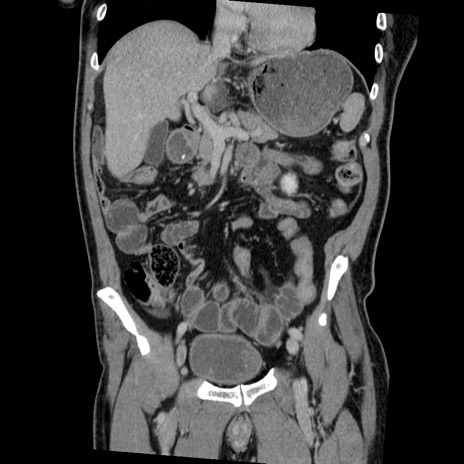

横断像

【症例】50歳代男性

【主訴】腹痛

【現病歴】AVMからの被殻出血のため回復期リハ病棟入院中。 本日午後3時頃急に下腹部痛が出現した。

【既往歴】AVM、被殻出血、虫垂炎、高血圧

【身体所見】意識晴明、左半身不全麻痺、会話の理解は良好、36.5°C、腹部:膨隆、全体に板状硬、下腹部正中に圧痛点あり、反跳痛-、筋性防御不明、右下腹部にope scar

【データ】WBC 9400、CRP 0.06